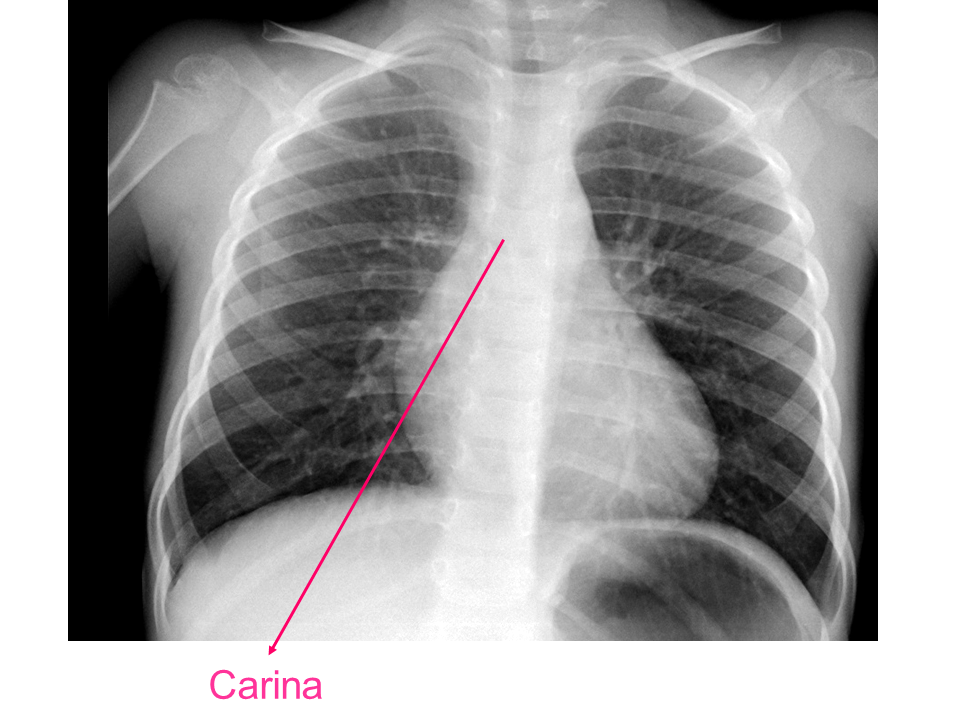

Para una adecuada lectura sistemática de la radiografía de tórax, debemos conocer la anatomía radiológica básica e identificar determinadas estructuras2.

• Carina